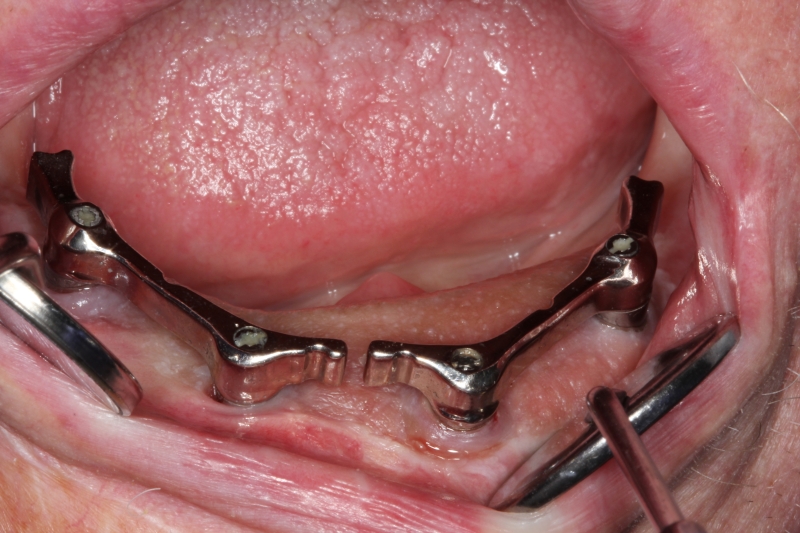

13/14 - Placement of bars for fixation of the prosthesis

Block augmentation with maxresorb®, collprotect® membrane & autologous bone blocks - Prof. Dr. Dr. D. Rothamel